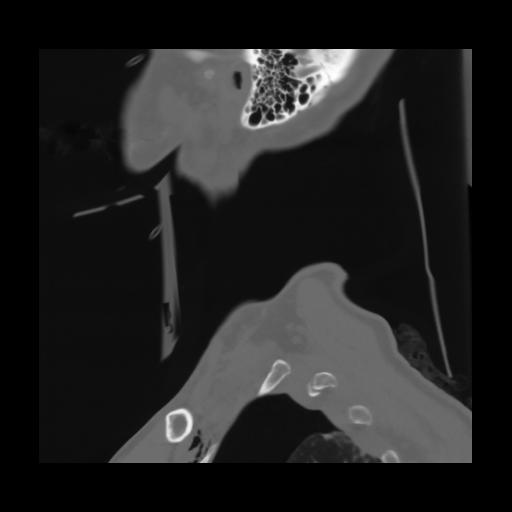

14 P.BLANDAS,,Sagittal,2.000,P.BLANDAS,Sagittal,